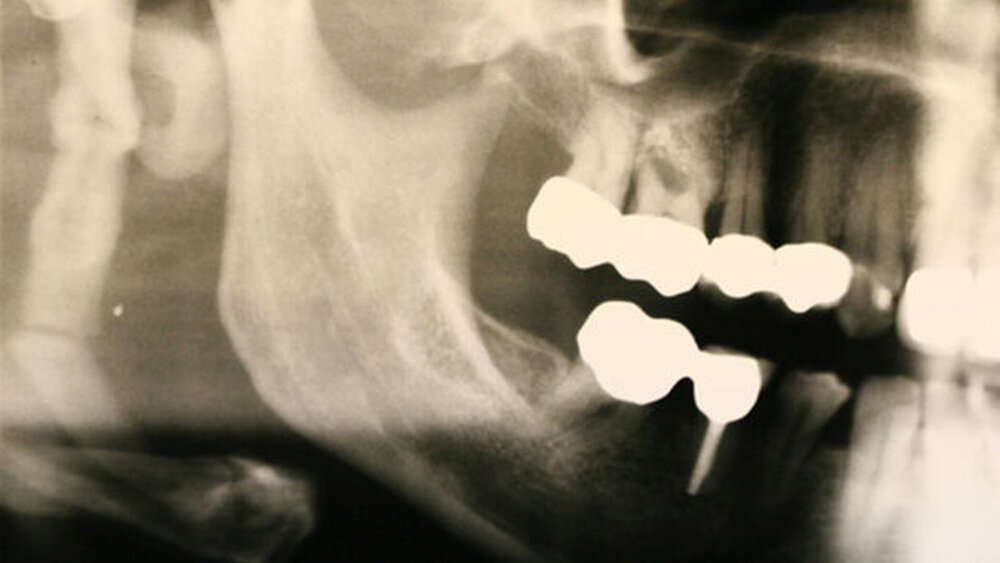

Das Orthopantomogramm zeigte einen signifikant vergrößerten Processus styloideus (47 x 11 mm) mit zusätzlich kompletter Verknöcherung des Ligamentum stylohyoideum rechtsseitig (Abbildung 1). Die Kiefergelenkfunktionsaufnahme (TM1) erbrachte den gleichen Befund (Abbildung 2).